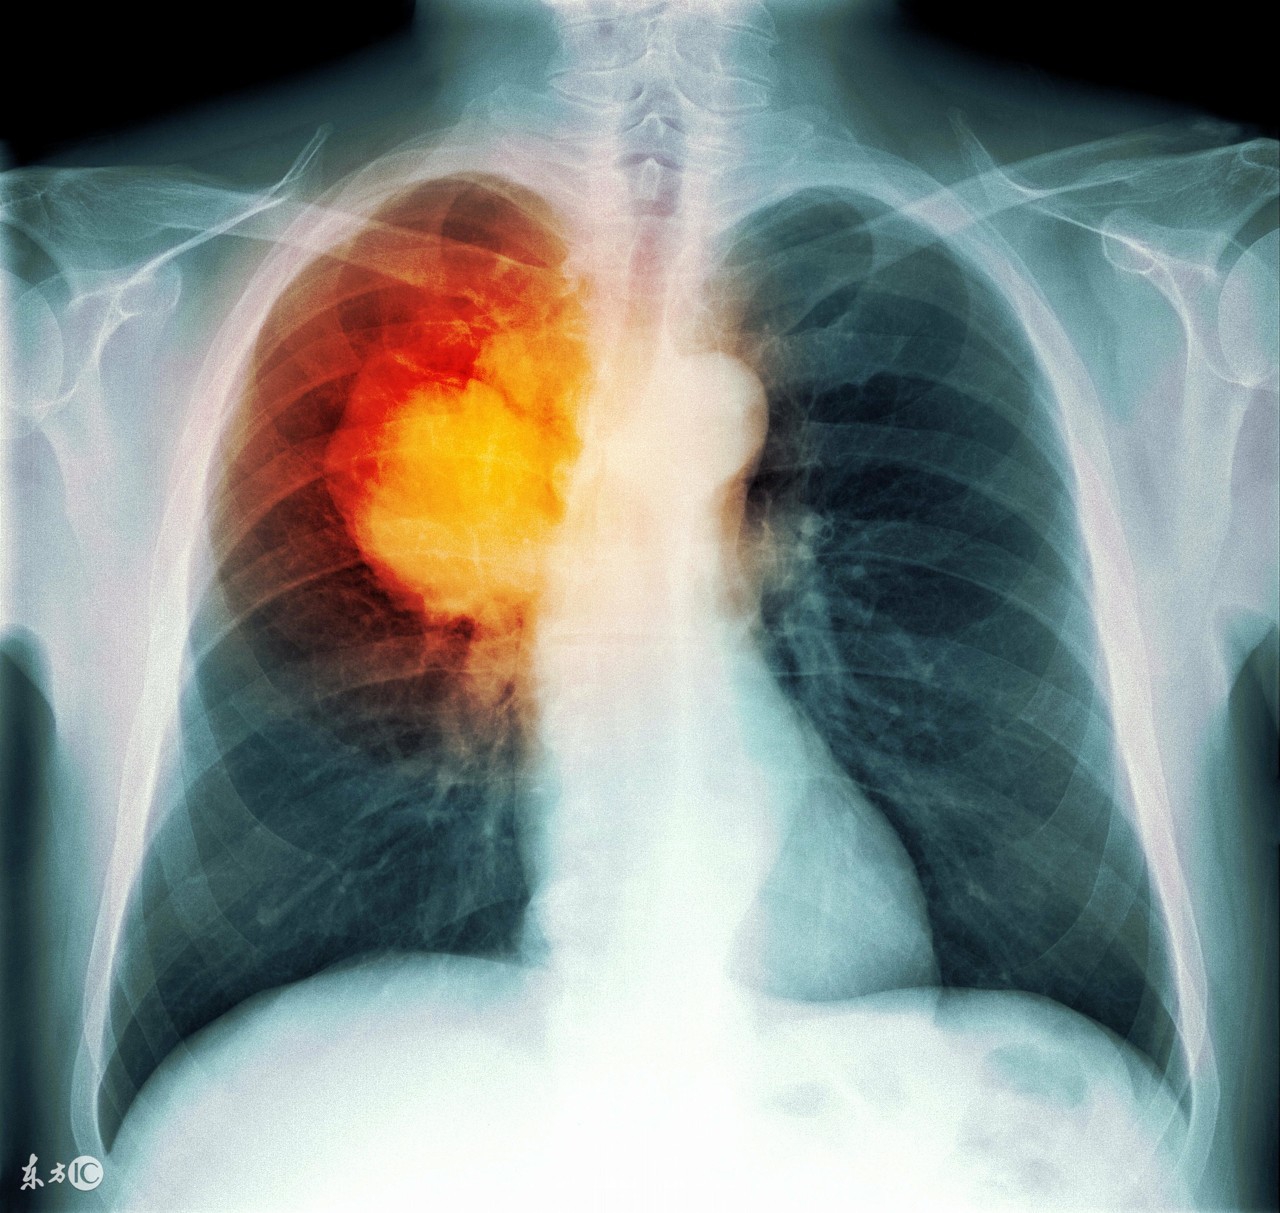

那么早期癌症很多是可以治愈的,晚期呢?尤其是发病率相当高的晚期肺癌呢?

肺癌晚期在早几年有转移的话确实没有特别好的治疗手段,因为如果发生了转移,那就意味着不能做手术,不能手术病灶就得不到有效的控制,生存期就很有限,现在各国投入了大量的人力物力进行研究肺癌药物,全世界出现了越来越多的治疗肺癌的靶向药物和免疫药物,比如易瑞沙、特罗凯、9291,、凯美纳、PD-1等等,这些药物的出现大大增加了肺癌晚期患者的存活率,使得癌症由绝症逐渐转变为慢性病,和高血压、糖尿病等疾病一样可以得到有效控制,尽管不能一次性治愈,但是可以做到带瘤生存,这已经是全世界范围内的共同认识了。